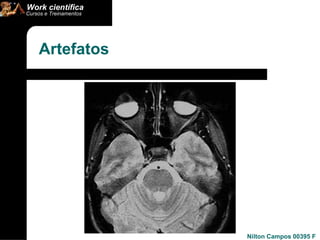

Artefatos